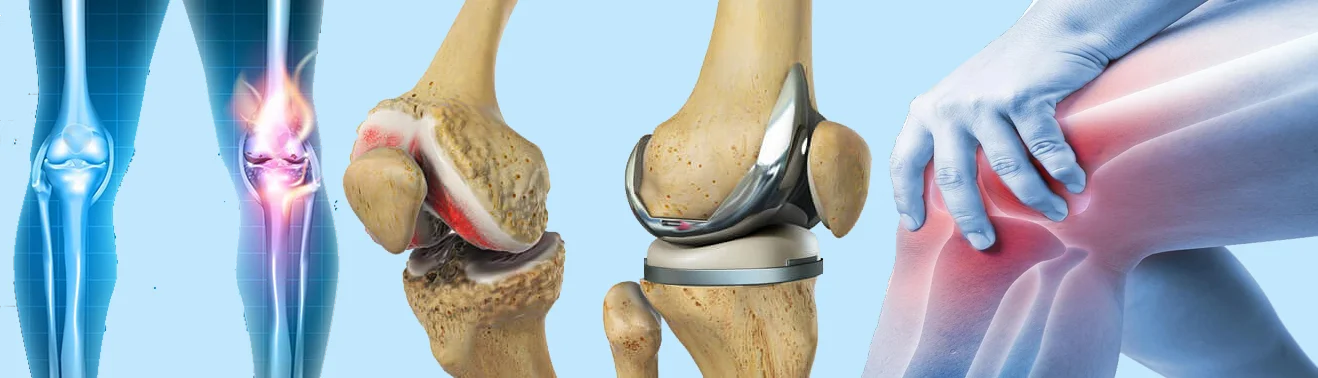

تعویض مفصل زانو یک جراحى بازسازى مفصل است که در آن سطوح فرسوده استخوان ران، درشتنى و کشکک برداشته مىشود و با قطعات مصنوعى از جنس فلز و پلیاتیلن جایگزین مىگردد. هدف اصلى این روش کاهش درد مزمن، اصلاح تغییر شکل زانو و بازگرداندن دامنه حرکتى کاربردى براى راه رفتن، نشستن و برخاستن است. برخلاف تصور عموم، این جراحى فقط زمانى انجام مىشود که درمانهاى غیرجراحى مانند دارودرمانى، تزریقات، اصلاح سبک زندگى و فیزیوتراپى دیگر پاسخگو نباشند.

پروتزها به طور کلى به دو نوع نیمه و کامل تقسیم مىشوند. در تعویض نیمه مفصل زانو فقط یک بخش آسیبدیده تعویض مىشود که براى بیماران با آرتروز محدود مناسب است. در تعویض کامل مفصل زانو هر سه بخش مفصل شامل بخش داخلى، خارجى و کشکک بازسازى مىشود و بیشتر براى آرتروز پیشرفته کاربرد دارد.

نیاز به تعویض مفصل زانو معمولا در افراد مبتلا به آرتروز شدید، روماتیسم پیشرفته یا آسیبهاى گسترده مفصلى مطرح مىشود. بیمارانى که درد شبانه دارند، راه رفتنشان محدود شده و با دارو و فیزیوتراپى بهبود قابل توجه نمىیابند، کاندیداهاى بالقوه این جراحى هستند. همچنین کسانى که تغییر شکل واضح در زانو مانند پرانتزى یا ضربدرى شدن دارند، اغلب نیازمند مداخله جراحى مىشوند.

جراحى معمولا بین یک تا دو ساعت طول مىکشد و تحت بیهوشى عمومى یا نخاعى انجام مىشود. جراح با برش کنترلشده به مفصل دسترسى پیدا مىکند، سطوح فرسوده را برمىدارد و پروتز را با سیمان استخوانى یا بدون سیمان ثابت مىکند.

پس از قرار دادن قطعات، دامنه حرکت مفصل بررسى مىشود تا از ثبات و لغزش مناسب اطمینان حاصل گردد. در پایان، زخم بخیه زده مىشود و بیمار به بخش ریکاورى منتقل مىگردد. شروع زودهنگام فیزیوتراپى زانو معمولا از همان روز یا روز بعد انجام مىشود.